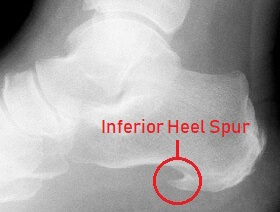

Foot bone spurs are areas of extra bone growth and are the most common cause of a hard lump on bottom of foot, usually on the heel or metatarsals.

Symptoms: Hard lump bottom of foot, sharp, stabbing pain when standing or walking.

Causes: Repetitive stress, tight shoes, injuries, arthritis or biomechanical changes.

Treatment: Exercises, orthotics, medication, and sometimes surgery.

See the Bone Spurs article for full treatment details.